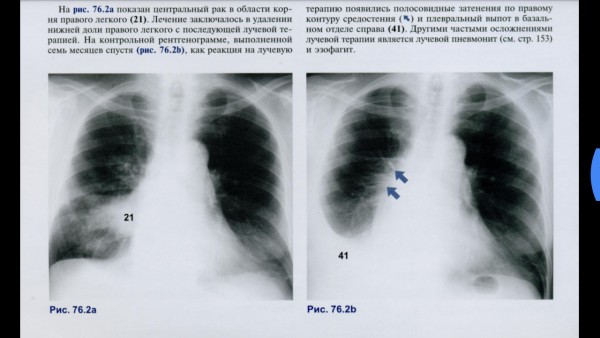

Сгущение легочного рисунка - это патологическое состояние, характеризующееся увеличением толщины или интенсивности легочных тканей на рентгеновских снимках. Обычно такое сгущение свидетельствует о наличии воспалительных процессов, инфекций, опухолей или других заболеваний в легких. Диагностика и дальнейшее лечение требуют индивидуального подхода к каждому пациенту, поэтому важно обратиться к квалифицированному врачу для получения точного диагноза и назначения соответствующего лечения.